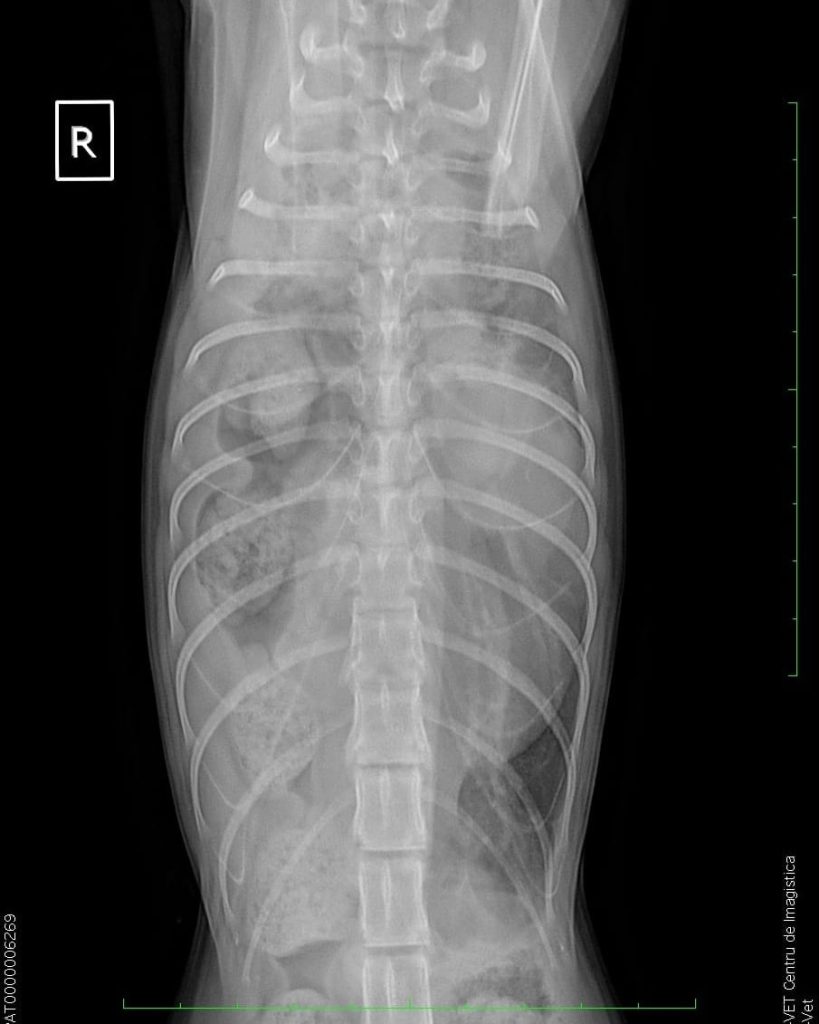

Așa cum se poate vedea pe radiografii, pisoiul are o hernie diafragmatică, organele sunt amestecate în cavitățile abdominală și toracică. Fără operație va muri.

Este plin de materii fecale. Va intra de urgență în operație la Radius Vet.